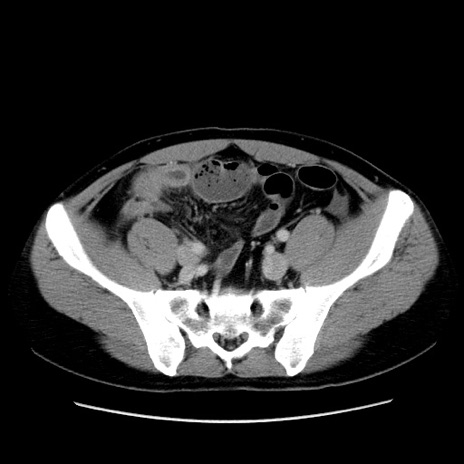

冠状断像